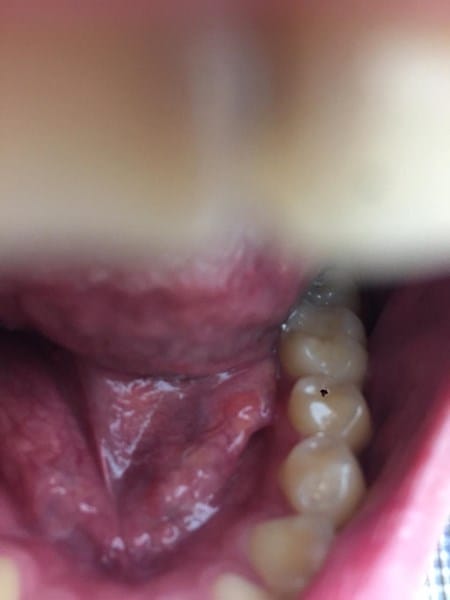

¿Siento cómo una ampolla debajo en la base de la boca debajo de la lengua? Que puede ser

Estuve leyendo y parece un mucocele no lo se, no me molesta ni nada no duele, solo cuando muevo mucho la lengua tocándomelo aveces si como que molesta. Pero en general si no me paso la lengua por ahí es como si no existiera, resulta que me traumó mucho con las cosas que aveces tengo.

al lado de la brusca que tiene la camara se ve como una ampolla.